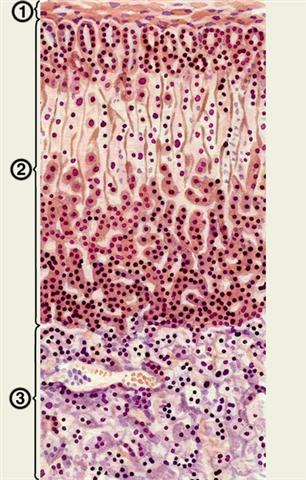

Рис. 3. Гистологическое строение надпочечника: 1 — собственная соединительнотканная капсула надпочечника; 2 — корковое вещество; 3 — мозговое вещество.